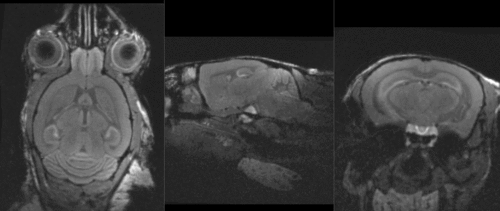

shown are, from left to right, panels of axial, sagittal and coronal views.

original, not RAS

original,after reorientation into RAS